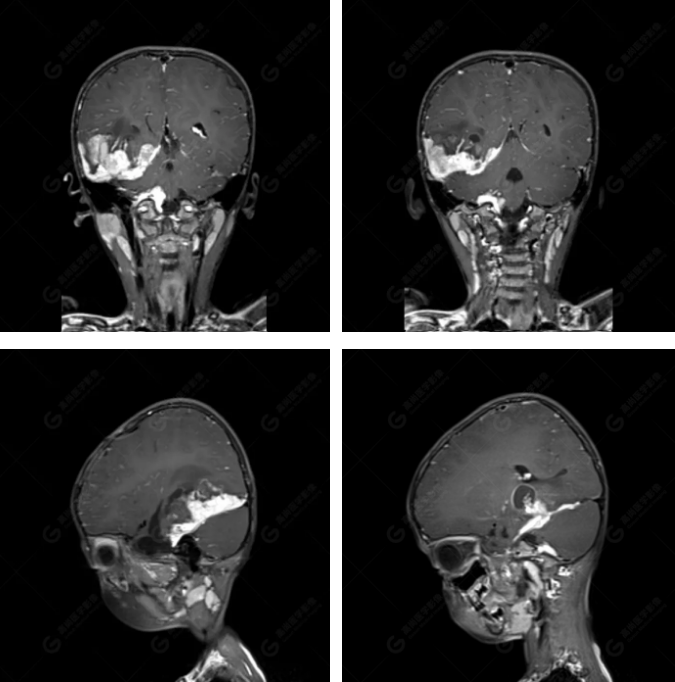

右側(cè)顳葉腫瘤切除術(shù)后(具體不詳):右側(cè)顳部骨質(zhì)不連續(xù)呈術(shù)后改變,右側(cè)顳葉術(shù)區(qū)見(jiàn)片狀長(zhǎng)T1長(zhǎng)T2信號(hào)影,F(xiàn)LAIR呈低信號(hào);術(shù)區(qū)后方右側(cè)顳枕葉見(jiàn)一巨大占位性病變影,邊界欠清,大小約6.2×5.8×4.3cm(前后×左右×上下),信號(hào)不均勻,T1WI呈等稍低信號(hào)間雜少許高信號(hào),T2WI呈高稍低混雜信號(hào),DWI示部分病灶彌散受限,相應(yīng)ADC圖減低,磁敏感序列見(jiàn)部分呈極低信號(hào),增強(qiáng)掃描可見(jiàn)明顯不均勻強(qiáng)化,鄰近硬腦膜及小腦幕增厚并明顯強(qiáng)化;另延髓右前方及右側(cè)橋小腦角區(qū)見(jiàn)一不規(guī)則形異常信號(hào)影,大小約3.2×1.3×3.7cm(左右×前后×上下),呈長(zhǎng)T1稍長(zhǎng)T2信號(hào),F(xiàn)LAIR呈等信號(hào),DWI未見(jiàn)受限,增強(qiáng)后明顯均勻強(qiáng)化,鄰近腦膜明顯強(qiáng)化。鄰近腦實(shí)質(zhì)及右側(cè)顳角明顯受壓;左側(cè)大腦半球未見(jiàn)局灶性信號(hào)異常,中線結(jié)構(gòu)稍左移。

右側(cè)顳葉腫瘤切除術(shù)后:現(xiàn)術(shù)區(qū)后方右側(cè)顳枕葉及延髓右前方占位,右側(cè)顳枕部硬腦膜及小腦幕明顯強(qiáng)化,結(jié)合既往影像資料,考慮為胚胎源性惡性腫瘤,如非典型畸胎樣/橫紋肌樣瘤(AT/RT)或原始神經(jīng)外胚層腫瘤(PNET)。